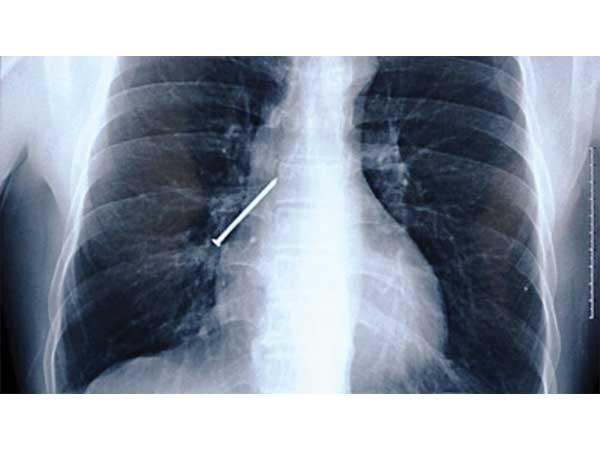

Nail

A carpenter in China accidentally swallowed a nail while he suddenly coughed. The procedure to remove the nail was quite a complicated one, as the nail had got stuck in the lung. Finally, after it was removed, the man had a speedy recovery.